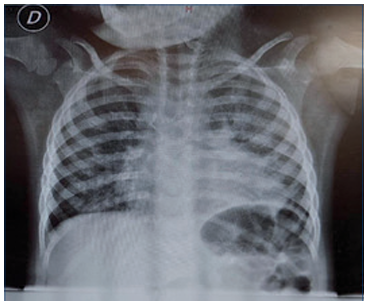

La radiografía de tórax mostró infiltrados algodonosos multifocales bilaterales y compromiso intersticial bilateral y difuso; el índice cardiotorácico era menor a 0,50 y la silueta cardiopericárdica no presentaba alteraciones (Figura 1). Ecocardiograma mostró CIA pequeña sin hiperflujo.

Figura 1 Radiografía de tórax, enfoque antero-pos terior. Infiltrados algodonosos multifocales bilate rales y compromiso intersticial bilateral y difuso, silueta cardiopericárdica sin alteraciones.